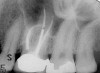

Figure 4 through Figure 10 depict several teeth that have conservative accesses while still allowing the clinician to adequately instrument and clean each tooth to achieve effective root canal therapy. The success of these cases still hinges on the proper cleaning and shaping of the root canal system, and while conservative accesses are desirable, too small of an access can lead to missed canals, poor instrumentation, improper cleaning, and, ultimately, a failed procedure.

Fig 4. Endodontic therapy on molar with four canals.

Figure 4